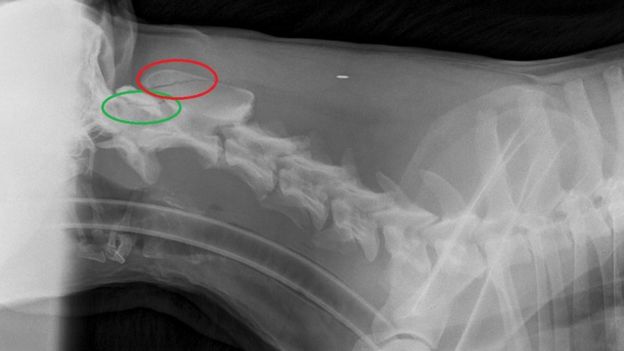

An X-ray released by the vet who treated the dog showed the extent of his injuries - two clear fractures.

"X-rays revealed that he had fractured two vertebrae in his neck," she said.